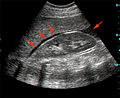

The hepatorenal recess[1] (subhepatic recess, pouch of Morison or Morison's pouch) is the space that separates the liver from the right kidney. As a potential space, the recess is not filled with fluid under normal conditions. However, fluid can collect in this space in circumstances where the abdomen fills with fluid, such as hemoperitoneum. This fluid may be seen on ultrasound or computed tomography (CT scan).

Since it is a potential space, the hepatorenal recess is not normally filled with fluid. However, this space becomes significant in conditions in which fluid collects within the abdomen (most commonly ascites and hemoperitoneum). The intraperitoneal fluid, be it blood, ascites, or dialysate, collects in this space and may be visualized, most commonly via ultrasound or computed tomography (CT) scanning. As little as 30 or 40 ml of fluid in the abdominal cavity may be visualized in this space.

Early visualization of fluid in the hepatorenal recess on FAST scan may be an indication for urgent laparotomy.[2]